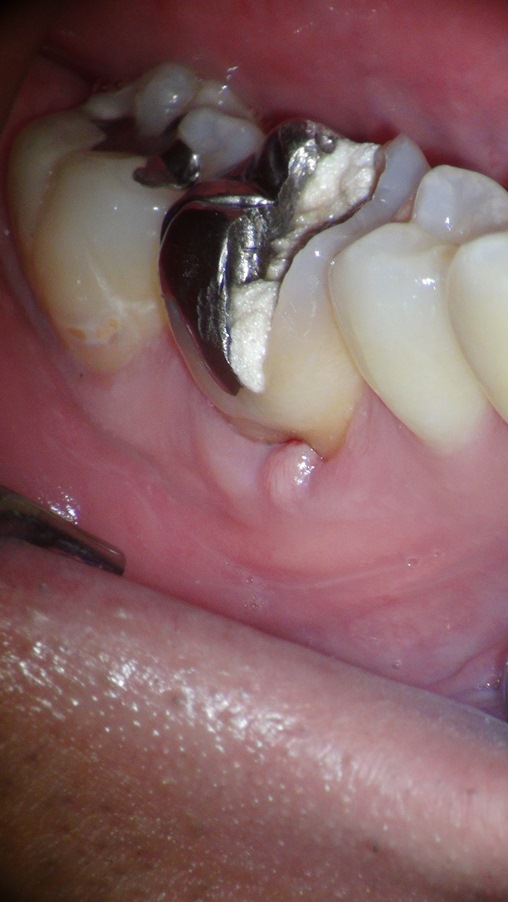

こちらの患者さんは、10年以上前に治療したところが、急に痛み出した、そして歯肉も腫れていると来院されました。お口の中を拝見させていただくと治療途中の歯が・・・。聞けば症状が出た後、地元の歯医者さんで2、3回治療をしたが回復の兆しがないことこれでダメなら抜歯!と言われたことからネットで調べて当クリニックを受診したとのこと。

確かに歯肉は腫れており、歯に圧力が加わると痛みがあるとのこと。